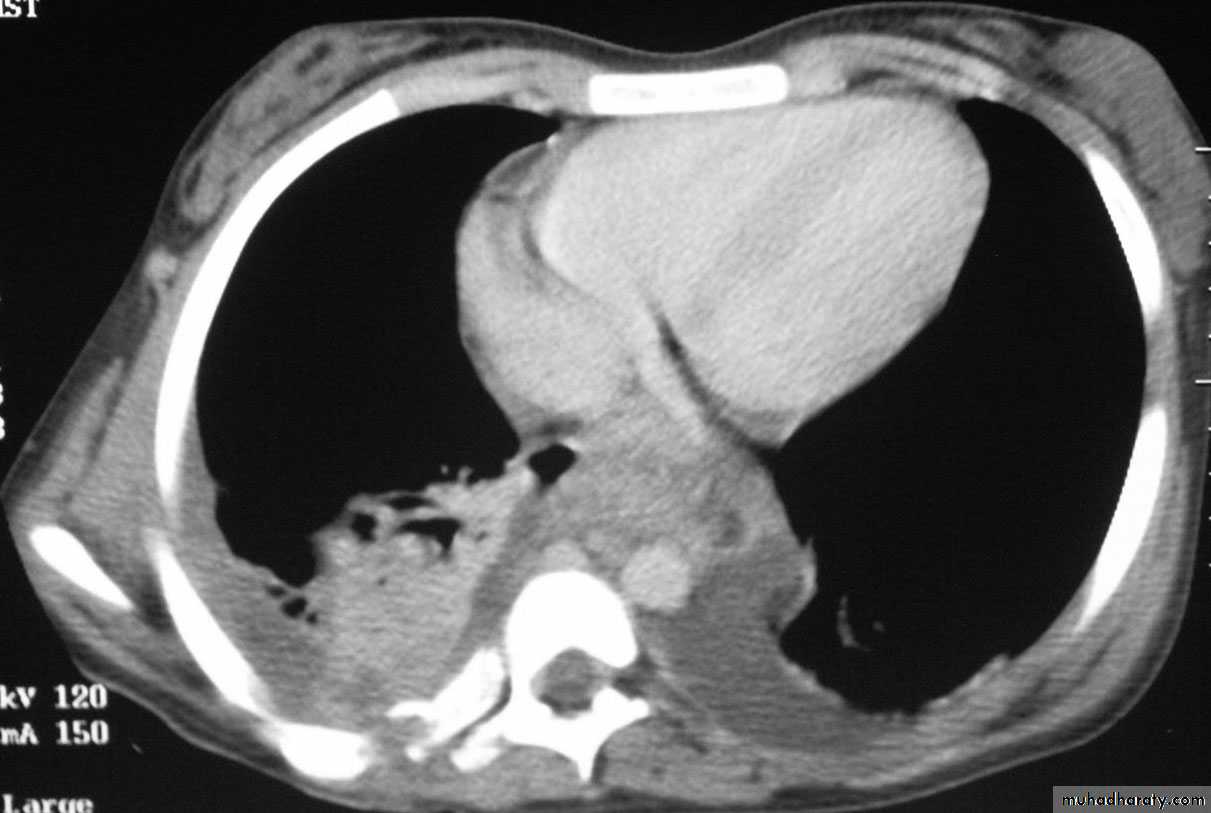

The main aims of investigations are to confirm the diagnosis, establish the histological cell type and define the extent of the disease.1- CXR: common radiological features of lung cancer:

Pleural effusion.

5- CT of chest; characterize lung lesion, staging of cancer, identify lymph nodes involvement, direct bronchoscope to the best area of lung sampling, and direct percutaneous needle biopsy.